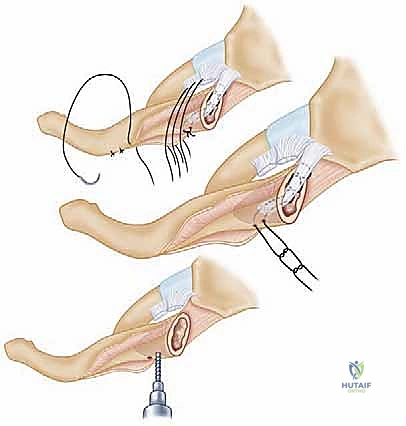

Modern stabilization relies on robust biological reconstruction. While primary repair of the capsule using suture anchors in the manubrium can augment the construct, a figure-of-eight graft reconstruction is the gold standard for restoring multiplanar stability. A semitendinosus or gracilis autograft (or allograft to minimize donor site morbidity) is preferred due to its length and tensile strength.

Drill holes, typically 4.0mm to 4.5mm in diameter, are meticulously created. In the medial clavicle, two holes are drilled from anterior to posterior, approximately 1 cm lateral to the articular margin and 1 cm apart. In the manubrium, two corresponding holes are drilled. Critical Step: When drilling the manubrium and the clavicle, a malleable retractor or a broad periosteal elevator must be placed deep to the bone to protect the mediastinal structures from the drill bit plunging. The drill must always be directed from anterior to posterior, with precise control.

The graft is then passed in a figure-of-eight configuration. Suture passing wires or curved shuttles are used to navigate the graft through the osseous tunnels. The graft is tensioned with the clavicle held in anatomical reduction (often requiring downward and posterior pressure on the medial clavicle). The graft limbs are then sutured to themselves and to the surrounding periosteal tissues using heavy, non-absorbable, braided sutures.

Some modern techniques utilize a "docking" method, where the graft is fixed into blind-ended sockets using biocomposite tenodesis screws, minimizing the need for posterior dissection and reducing the risk to mediastinal structures. Regardless of the specific graft routing, the final construct must be rigidly stable through a functional range of motion on the operating table.

Following fixation, the previously tagged capsular flaps are repaired over the graft to provide secondary stabilization and soft tissue coverage. The sternocleidomastoid and pectoralis fascia are meticulously closed to eliminate dead space, and the skin is closed in a layered fashion.